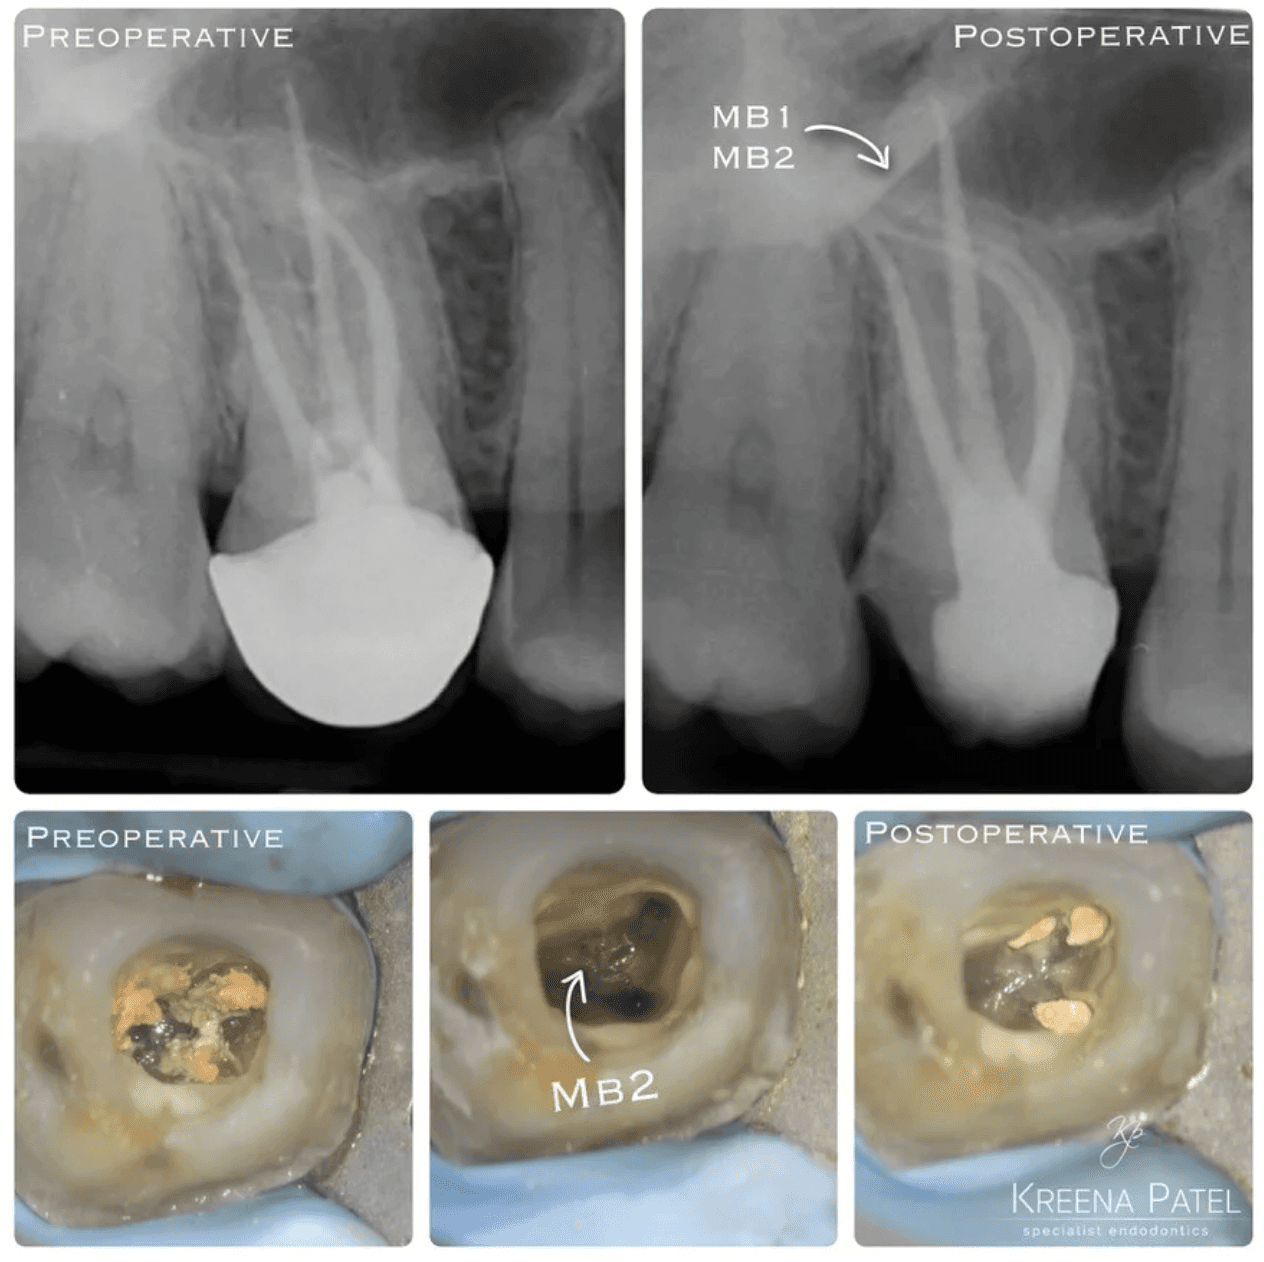

KREENA'S CASES